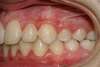

Vues avant le traitement